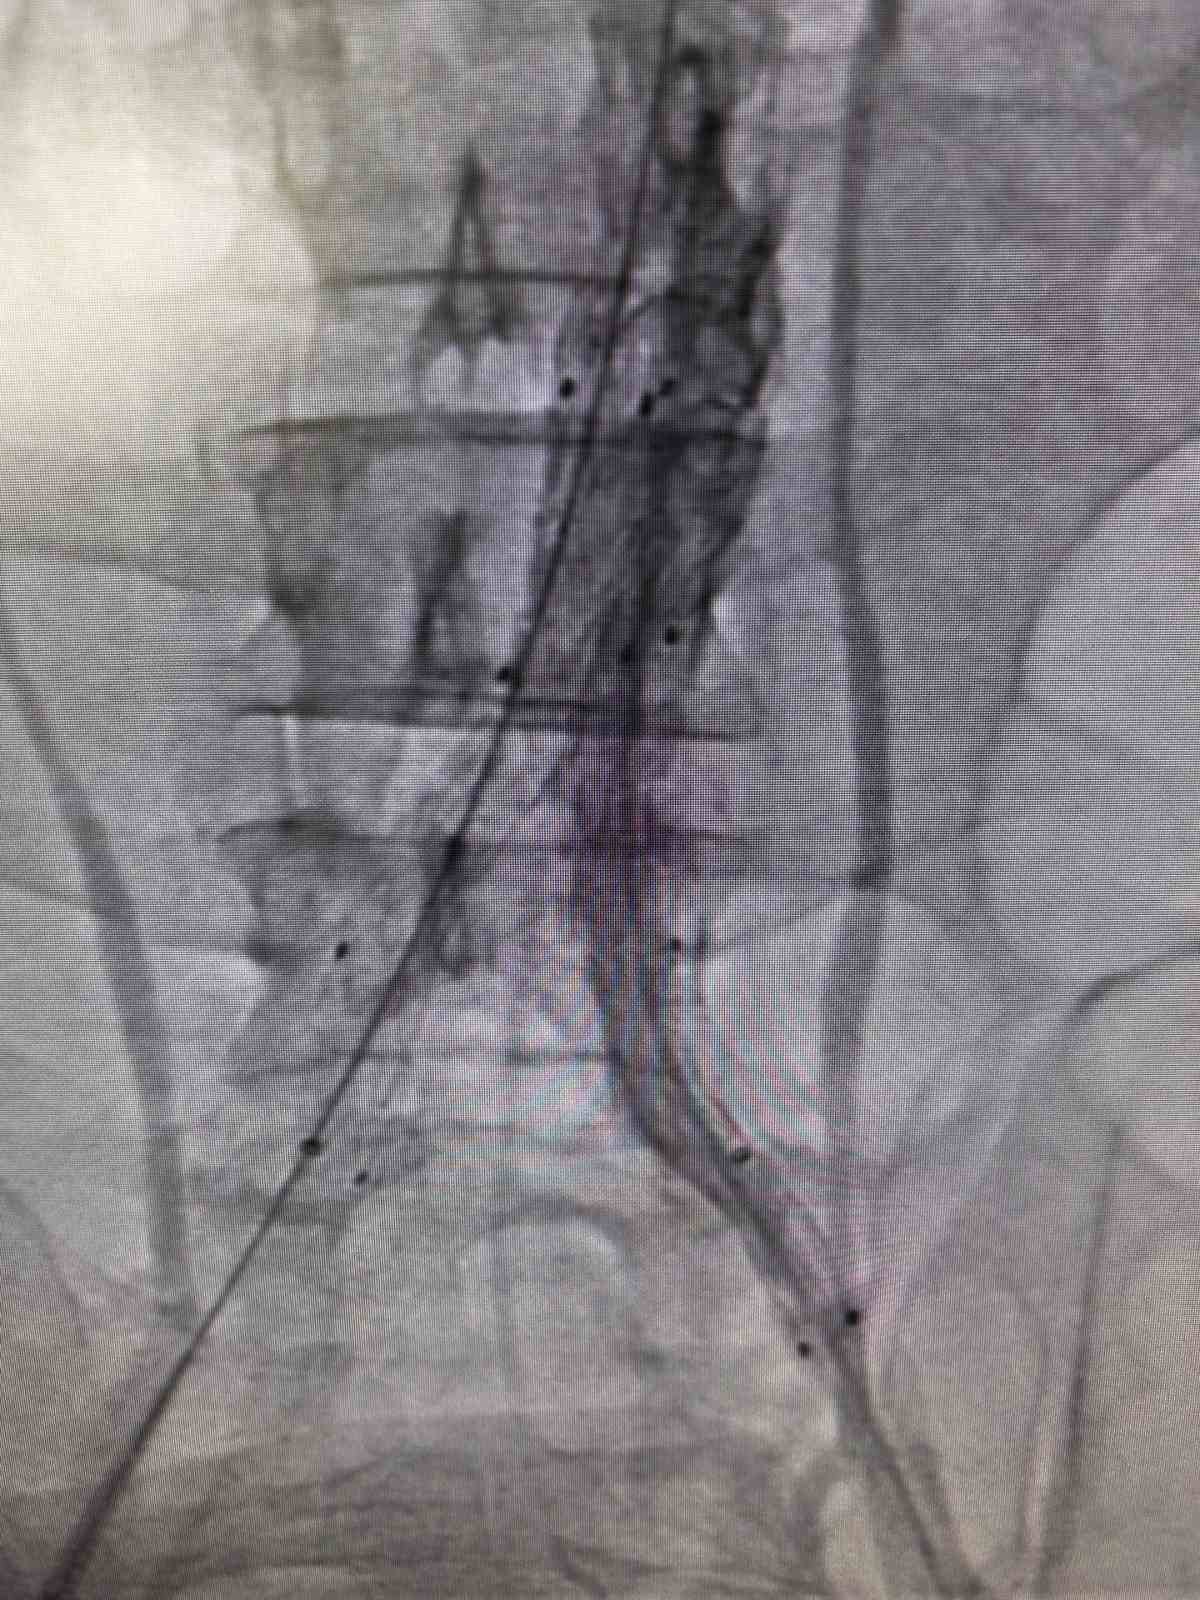

Bilecik’te hayat kurtaran kapalı damar operasyonu

Bilecik Eğitim ve Araştırma Hastanesi’nde 39 yaşındaki Mehmet D.’nin ana atardamarındaki yırtık, kapalı yöntemle stent yerleştirilerek başarıyla onarıldı.

Bilecik Eğitim ve Araştırma Hastanesi'ne şiddetli sırt ve karın ağrısı şikâyetiyle başvuran 39 yaşındaki Mehmet D.'nin ileri tetkiklerinde, kalpten çıkan ana atardamarın iç duvarında hayati tehlike oluşturan bir yırtık tespit edildi. Daha önce farklı sağlık kuruluşlarına başvuran hasta, acil serviste yapılan detaylı inceleme sayesinde doğru tanıya ulaştırıldı.

Müdahale: Kapalı yöntemle damar içten onarım

Kalp ve damar cerrahisi ekibi tarafından acil değerlendirilen hasta, Kalp ve Damar Cerrahisi Uzmanı Op. Dr. Elmas Üreyen tarafından kapalı yöntemle tedavi edildi. Damar içinden girilerek gerçekleştirilen işlem sırasında yırtılan ana damarın içine özel bir stent yerleştirilerek damar içten onarıldı; açık ameliyata gerek kalmadan işlem tamamlandı ve hasta kısa sürede rahatlama gösterdi.

Sonuç ve takip

Tedavi sonrası yakından izlenen hastanın ağrıları tamamen geçti, genel sağlık durumu iyi gözlendi ve kontrolleri sorunsuz seyrettiği için hasta sağlıklı bir şekilde taburcu edildi.